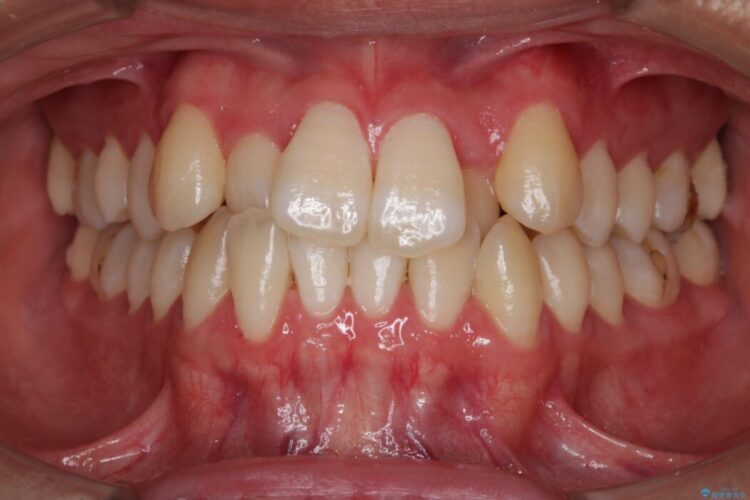

上顎歯列弓のガタガタを治療したいとのことで来院されました。

前に出ていた前歯や目立つ八重歯(3番目の歯)もきれいに並び、奥歯の虫歯治療も並行して行ったため、機能面でも見た目的にも良くなり満足していただきました。